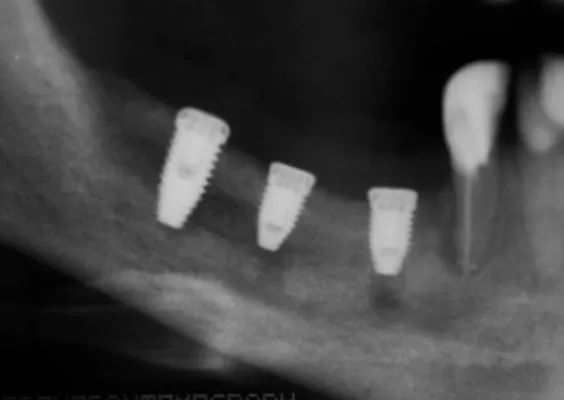

ZABIEGI REGENERACJI KOSTNEJ WOKÓŁ WSZCZEPIANYCH IMPLANTÓW

Sterowana regeneracja kości GBR przy użyciu biomateriałów oraz membran zaporowych. Procedury te są stosowane w sytuacji niedostatecznej ilości kości, skutkującej odsłonięciem gwintu, podczas gdy wszczepiamy implanty stomatolo-giczne lub też jako zabiegi poprzedzające ich wprowadzenie.

Metoda rekonstrukcji kostnej w oparciu o indywidualnie drukowane siatki z tytanu dla implantacji wszczepów śródkostnych stosowana jest najczęściej jako dwuetapowa. W pierwszym etapie odbudowywana jest kość, natomiast implanty wszczepiane są po okresie 4–6 miesięcy. Na wgojenie implantów oczekujemy od 4 do 6 miesięcy w zależności od miejsca ich lokalizacji. Siatka tytanowa po spełnieniu swojej funkcji rusztowania dla odbudowującej się kości jest następnie usuwana w dniu wszczepienia implantu. Jeżeli kość spełnia odpowiednie warunki, istnieje możliwość zastosowania modyfikacji siatki tytanowej, która umożliwia jednoczesne wprowadzenie implantów wraz z odbudową kostną.

Przy zabiegu wszczepienia implantu nie zawsze niezbędna jest odbudowa kostna okolicy implantowanej. W sytuacji istnienia prawidłowej objętości kości we wszystkich wymiarach implantujemy bez odbudowy kostnej. Przy niedostatku kości w jednym z wymiarów warunkiem prawidłowego osadzenia i wgojenia implantu jest regeneracja kostna. Ma ona wpływ zarówno na względy biologiczne, czyli prawidłowe wgajanie się implantu, jak i względy funkcjonalne – brak retencji pokarmów pod prawidłowo uformowanymi koronami. Istotne dla pacjenta są również względy estetyczne, które osiąga się poprzez anatomiczne odtworzenie kształtu dziąsła rozpiętego nad odbudowaną kością, dające prawidłowe wyłonienie korony protetycznej odtwarzanego zęba. Uwzględnienie odtworzenia zarówno kości, dziąsła, jak i koron zębów daje w pełni estetyczne i funkcjonalne efekty, które najlepiej imitują własne uzębienie.